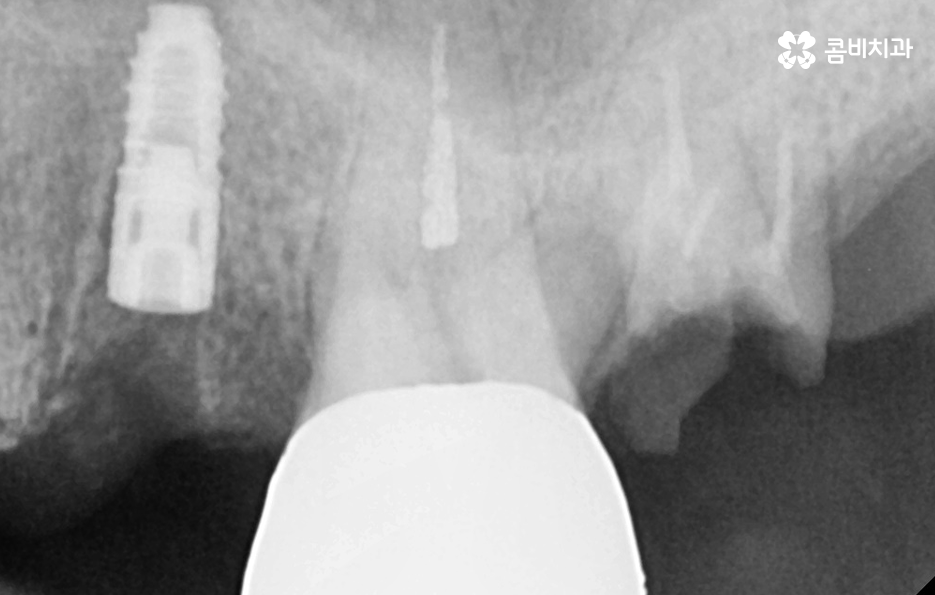

우리가 흔히 치아의 수명이 다했다고 판단하는 기준에서 치아의 뿌리 쪽 상태를 매우 중요하게 보고 있는데 치아의 구조에서 신경조직의 손상은 신경치료 후 크라운을 씌워서 보존 치료가 가능하지만 충치가 심하거나 충치가 뿌리까지 진행되어 심하게 손상된 경우에는 결국 발치하게 되는 것처럼 임플란트의 치료 원리는 잇몸 뼈에 임플란트의 인공치근을 식립하여 잇몸 뼈와의 골유착 과정을 통해 이름 그대로 인공치아의 역할을 수행하게 되기 때문에 임플란트의 인공치근이 잇몸 뼈가 안정적으로 골유착이 되는 것이 임플란트 치료의 관건이 될 수 있어요

따라서 자연치아로 따지면 치아 뿌리의 역할을 하는 것이 잇몸 뼈에 식립된 임플란트의 인공치근이 그 역할을 하고 있기 때문에 특히 어금니 처럼 저작력에 있어서 중요한 치아 부위에 임플란트를 식립할 경우에는 저작력을 감당하기 위해 그만큼 잇몸 뼈의 상태가 충분해야 하는데 잇몸 뼈의 두께와 깊이, 골질이 충분히 확보된 상태에서 임플란트를 식립해야 하므로 잇몸 뼈가 부족한 경우에 뼈이식을 추가적으로 진행하고 있어요